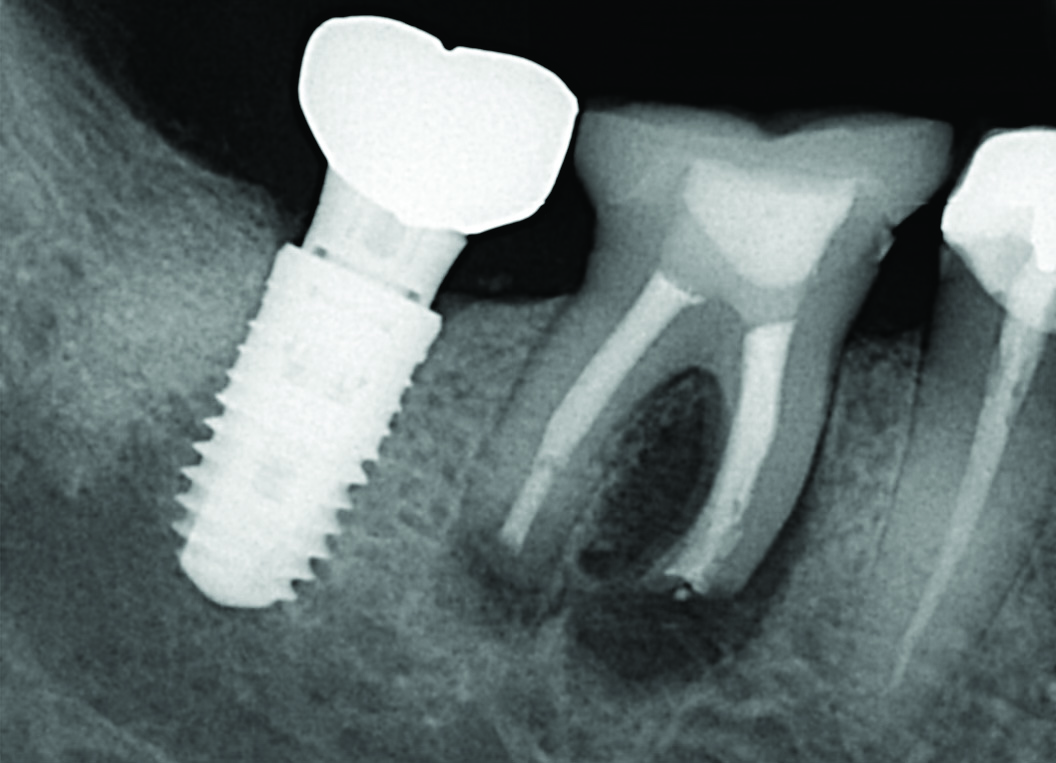

Fig 1 through Fig 4. Examples of multirooted teeth showing periradicular periodontitis and loss of periradicular bone support isolated to one root (indicated by red arrows). Fig 1: Tooth No. 3 distobuccal root with circumferential bone loss from the crestal bone height to the apex with stable mesiobuccal and palatal roots. Fig 2: Tooth No. 30 with a prior apical surgery showing bone loss surrounding a fractured mesial root. Fig 3: Tooth No. 19 with lateral and apical bone loss regions affecting a fractured mesial root. Fig 4: 3D CBCT imaging of tooth No. 3 depicting an apicomarginal bone loss defect affecting the mesiobuccal root with stable fused distobuccal and palatal roots.

Fig 4. Examples of multirooted teeth showing periradicular periodontitis and loss of periradicular bone support isolated to one root (indicated by red arrows). Fig 1: Tooth No. 3 distobuccal root with circumferential bone loss from the crestal bone height to the apex with stable mesiobuccal and palatal roots. Fig 2: Tooth No. 30 with a prior apical surgery showing bone loss surrounding a fractured mesial root. Fig 3: Tooth No. 19 with lateral and apical bone loss regions affecting a fractured mesial root. Fig 4: 3D CBCT imaging of tooth No. 3 depicting an apicomarginal bone loss defect affecting the mesiobuccal root with stable fused distobuccal and palatal roots.